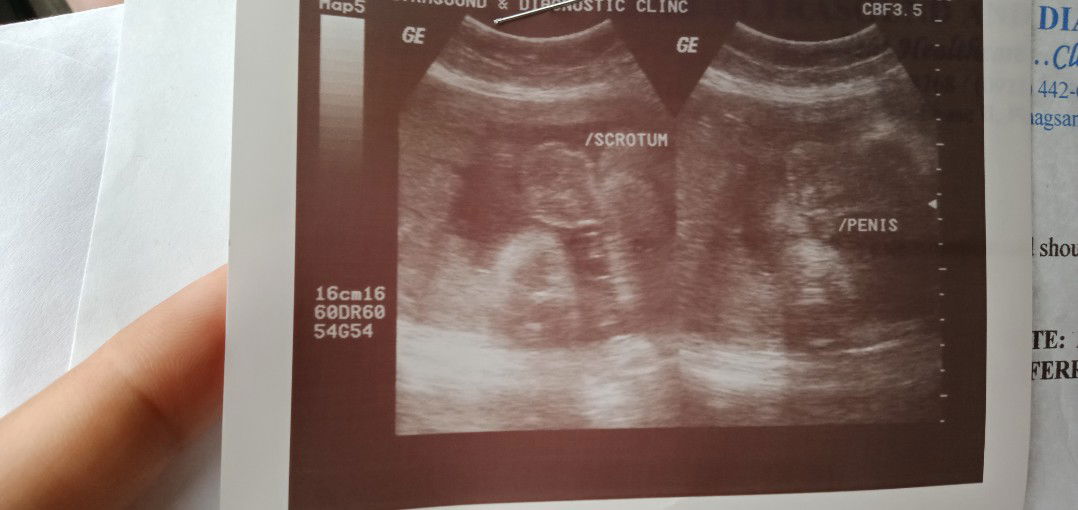

ultrasound share ??

nag paultrasound ako ng 6months 60% girl ????? tapos naninigas kasi tyan ko at lagi sumisiksik sa gilid . kaya sinabi ko sa obygyn ko . kaya pina ultrasound ulit ako okey nmn lahat .. hehehe ngaun naging boy 100%???? ihave a 2 girls and now 1 boy . ?????? pwede pa pala mabago un .?? sharekolang po .

mga momshie ... mag ng paultrasound po b ng 6 months at 60% na ung gender .. diba po wala n posibelidad n mabago un ..

hi mga mommy . ask ko lng po nag pa ultrasound po ako .. diba pg 60% na ung gender ni baby . di na un mg babago ?